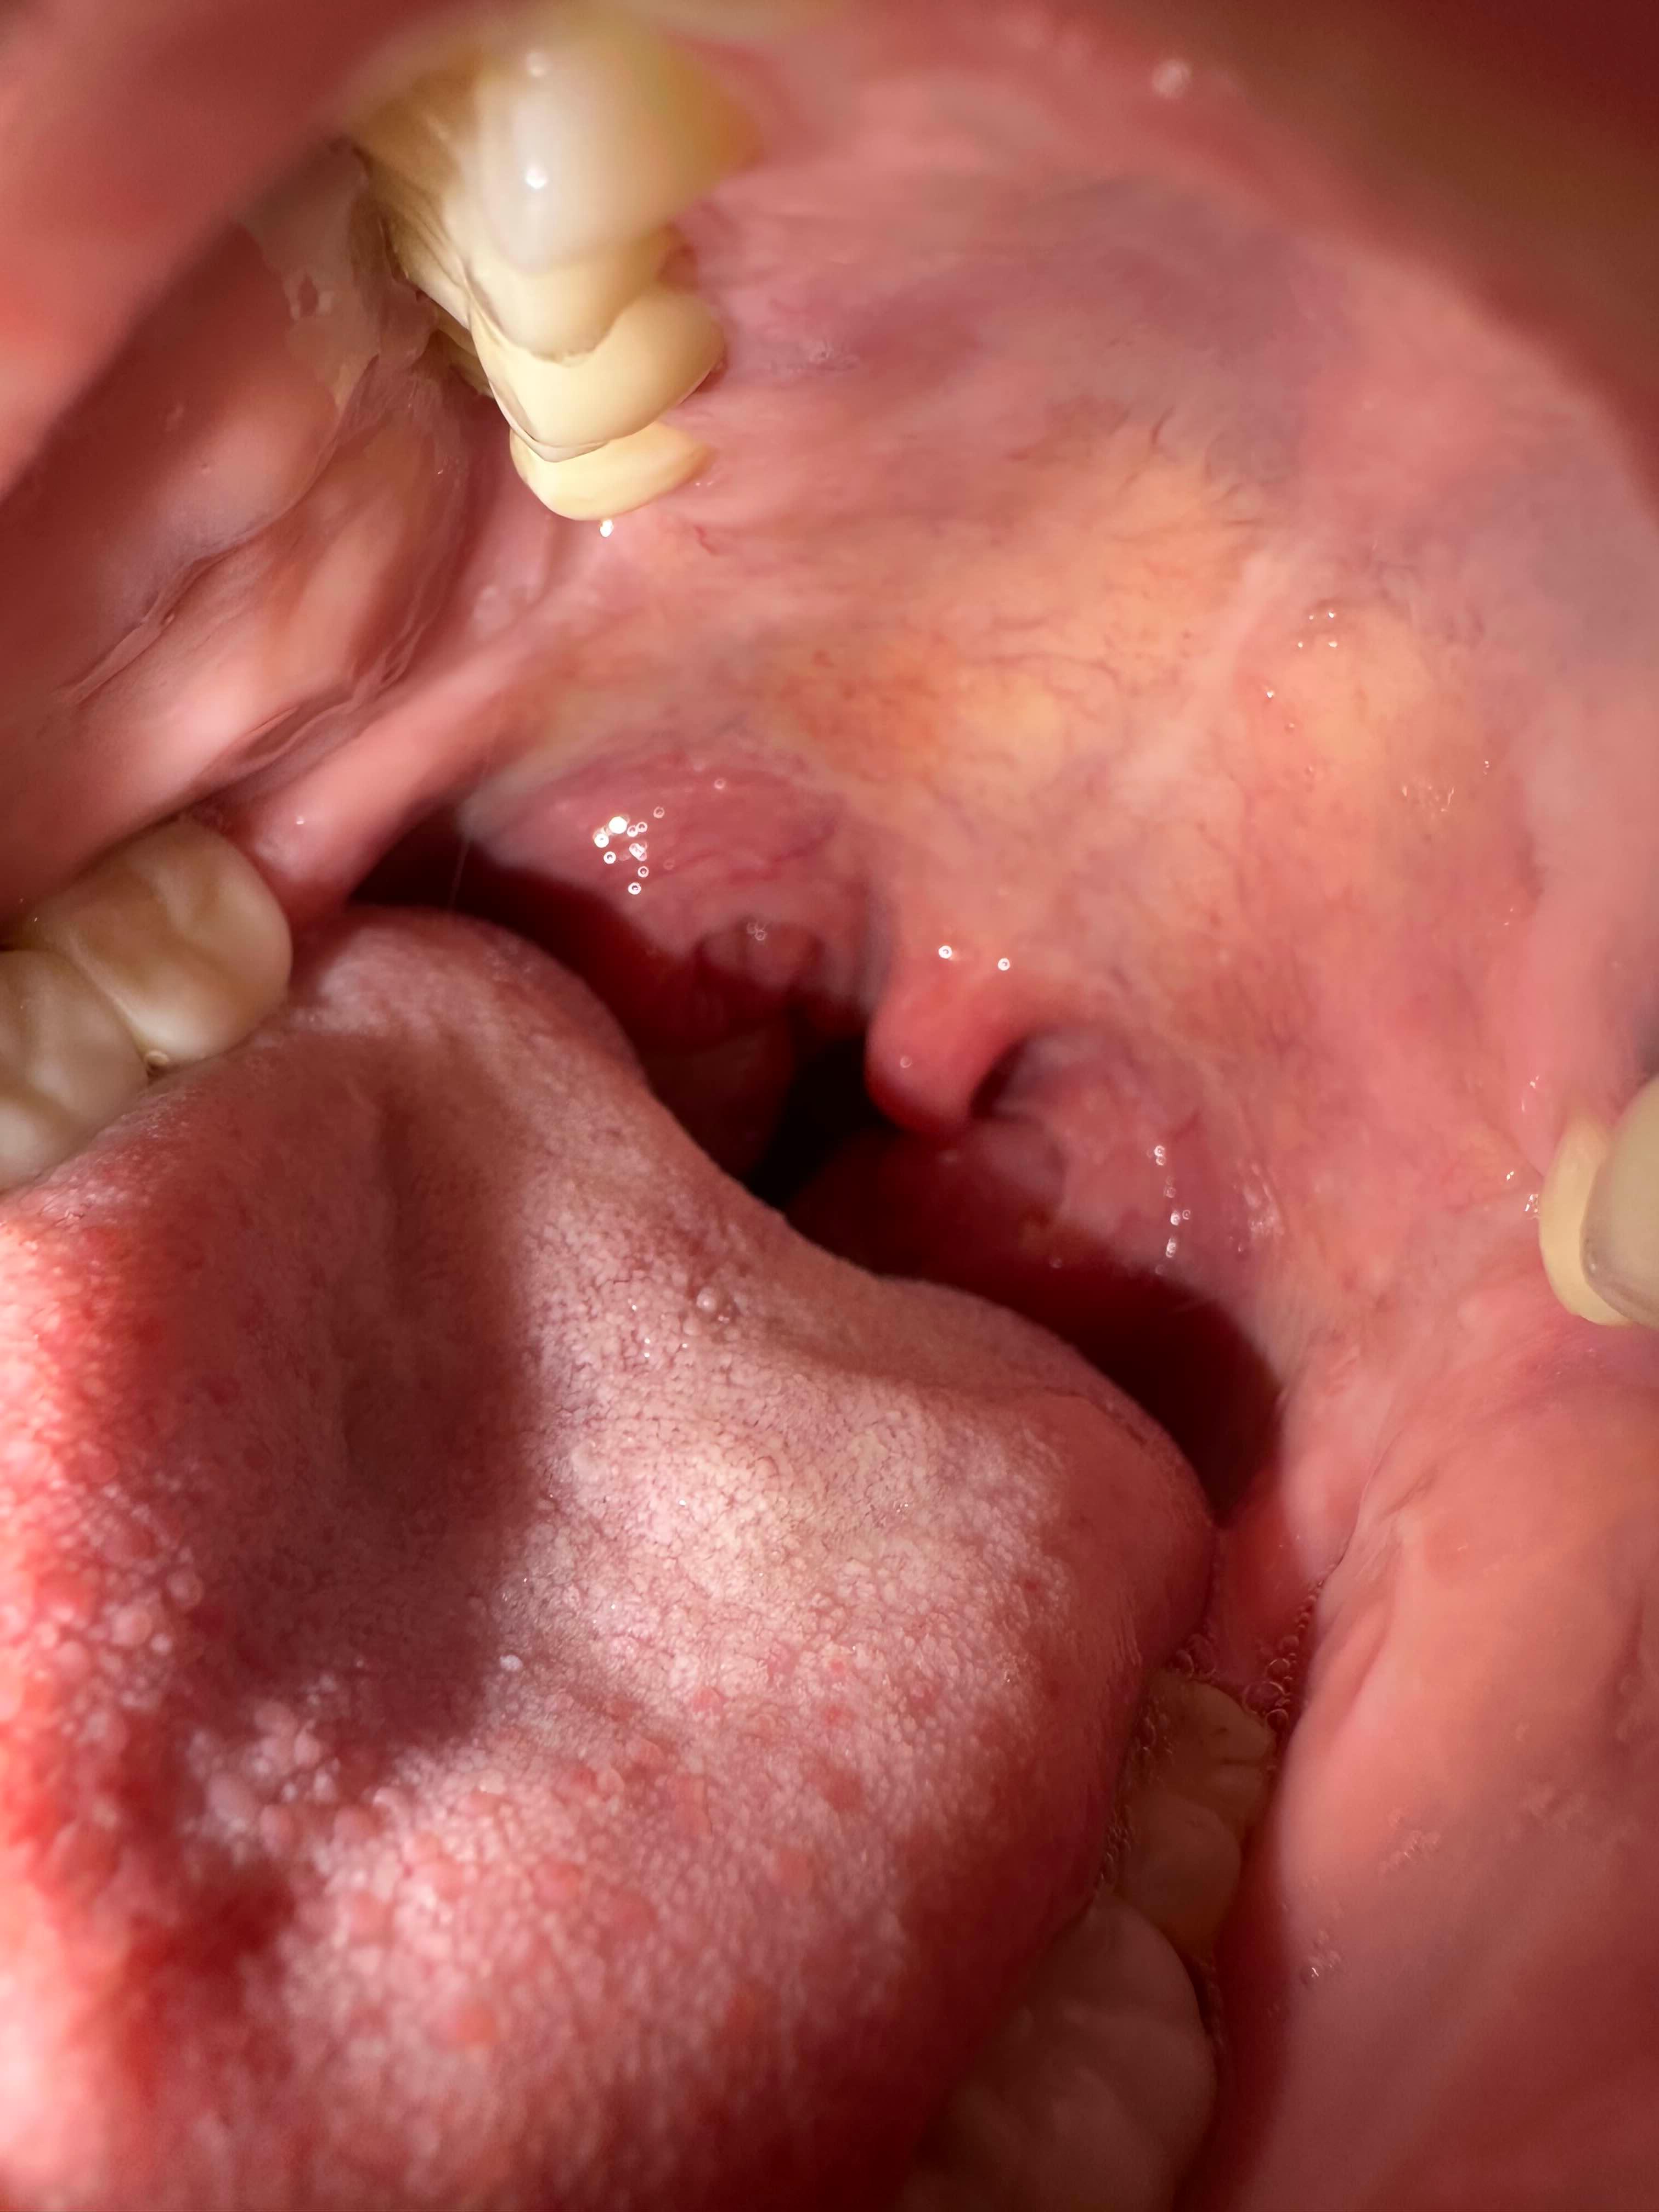

우선 전 사진을 보면

편도가 진짜큼.. ㅋㅋ

의사샘이 말하기전까지 정말 몰랐음

내가 이렇게 큰줄..

첨에 이렇게 크지도 않았는데

매번 편도염 걸리고, 면역떨어지고 피곤함누적되니

커진거😭